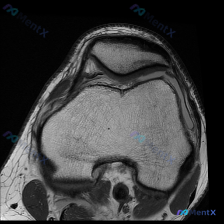

今天碰到一个很典型的「临床-影像矛盾」病例,整理出来和大家一起讨论一下。 病例核心信息 问题:临床高度怀疑膝关节软骨异常,仅提供1张膝关节MRI-T1序列轴位影像(髌股关节层面),要求读片分析。 影像读片结果: 1. 骨性结构:股骨远端、髌骨骨皮质连续,软骨下骨光滑,骨髓脂肪信号均匀,未见异常信号灶...

今天遇到一个有意思的读片问题:只给了一张膝关节轴位MRI,问这里有没有软骨异常,整理一下分析思路分享给大家。 基本病例/影像信息 提供的是膝关节单张轴位MRI扫描图像,可识别的解剖结构包括:前方的髌骨、中部的股骨内外侧髁与髁间窝、髌股关节间隙,以及周围部分软组织。 客观影像所见 1. 软骨结构:髌骨...

看到一份针对单张膝关节MRI的软骨异常评估咨询,整理了完整的分析思路分享给大家。 病例/影像基础信息 问题核心:用户提供单张膝关节轴位T1加权MRI图像,询问图像中是否存在软骨异常。 影像所见(基于提供图像): 1. 扫描层面为膝关节轴位,涵盖股骨远端滑车区与髌骨 2. 股骨髁、髌骨骨髓信号正常(T...

刚遇到一份有意思的膝关节影像病例,整理出来和大家分享一下思路。 病例基本信息 这是一份膝关节MRI T1序列轴位单张图像,核心疑问是评估是否存在「软骨异常」。 影像读片结果 1. 扫描层面是膝关节上部,主要显示髌股关节(髌骨+股骨滑车)和股骨髁 2. 髌骨软骨下骨、股骨髁骨皮质轮廓清晰,骨松质信号均...

病例读片:膝关节软骨异常的影像陷阱 先给大家看一下这份病例的基本影像资料:这是一张膝关节MRI-T1加权序列的轴位图像,扫描层面位于股骨远端髁间窝与髌股关节层面。 影像基本信息整理 1. 骨骼结构:股骨远端骨皮质、骨髓信号正常,髌骨形态完整,骨皮质连续,骨髓信号无异常; 2. 关节软骨:髌骨后方关节...